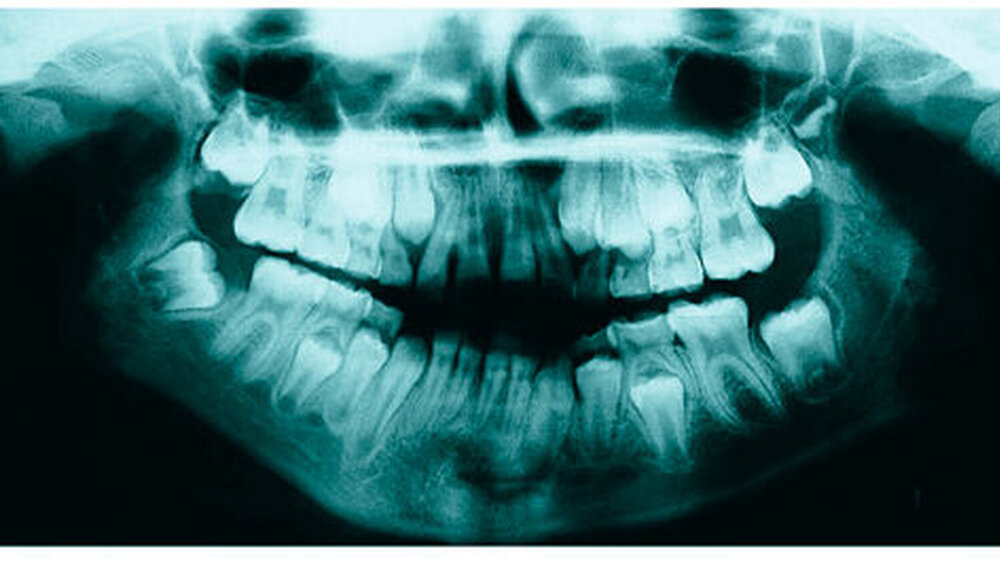

Bereits 2004 wies Carla Evans [Evans, 2005] auf das Risikomanagement bei Allgemeinerkrankungen hin und stellte am Beispiel der JIA dar, dass Unterkieferrücklagen und frontal offene Bisse aus der Kiefergelenkzerstörung entstehen können. Die Röntgenaufnahmen einer JIA-Patientin mit oligoartikulärer Form und Beteiligung des rechten Kiefergelenkes zeigen den typischen Verlauf sehr gut. Bei ursprünglich sehr dezenten Befunden, wie einer s-förmigen Mundöffnung von 44 mm, einer geringen Mittenabweichung um 2 mm nach rechts und einem frontal offenem Biss klagte sie über Schmerzen beim Essen, was den Anlass zur weiteren Diagnostik bot. Die erste Panoramaröntgenschichtaufnahme (Abbildung 1a-c) zeigt auf der rechten Seite einen abgeflachten Kondylus und eine bereits verstrichene Fossa condylaris. Ein Jahr später vermittelt das Fernröntgenseitenbild (Abbildung 1d) trotz fortschreitender kondylärer Resorption ein harmonisches Bild, während nach drei Jahren bei voranschreitendem Abbau des rechten Kondylus (Abbildung 1e) eine Rücklage der Mandibula und eine Bissöffnung manifest sind (Abbildung 1f).

Mithilfe der Panoramaröntgenschichtaufnahme lässt sich in bis zu 67 Prozent der Fälle bereits eine Kiefergelenkdestruktion bei Kindern mit JIA feststellen [Küseler et al., 1998; Twilt et al., 2004; Abramowicz et al., 2014]. Eigene Untersuchungen bestätigten die Eignung als Screening-Verfahren [Mäckelmann, 2008].

Bei 152 durchschnittlich 12-jährigen Rheumapatienten wurden die kondyläre Morphologie und Symmetrie beziehungsweise Asymmetrie im Vergleich zu einer Kontrollgruppe anhand der OPG analysiert. Zur Analyse erfolgte die Zuordnung zu vier morphologischen Graden je Kondylus (Abbildung 3a-d). Bei 45 Prozent der Rheumapatienten waren morphologische Veränderungen im Rahmen kondylärer Resorption unterschiedlicher Ausprägung zu finden. Die „Kontrollpatienten“ ohne JIA zeigten nur zu 14 Prozent formatypische Kondylen. Der Unterschied zwischen den beiden Gruppen war signifikant. Daher sollte bei der Routineauswertung von Panoramaröntgenschichtaufnahmen auf diese Anzeichen geachtet werden, insbesondere auch unter dem Aspekt, dass laut Assaf [2011] durchschnittlich 4,3 Jahre zwischen Erstmanifestation der JIA und Erstvorstellung in der Rheumasprechstunde des UKE liegen.